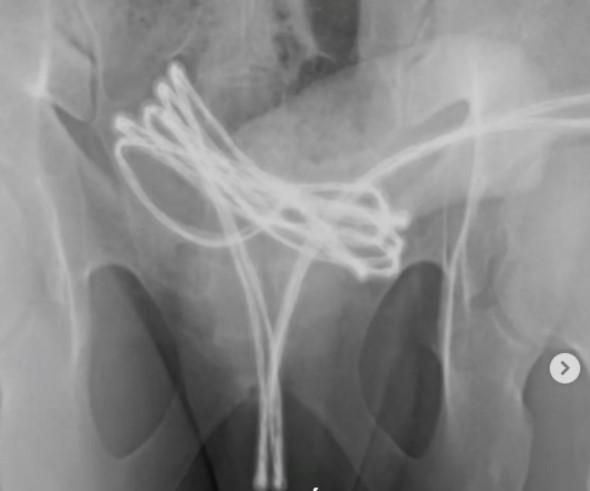

Um caso clínico publicado na edição de fevereiro da revista médica Cureus trouxe à tona uma prática pouco conhecida e altamente arriscada: a sondagem uretral , que consiste na introdução de objetos na uretra com finalidade s3xual . O relato, assinado por médicos da Faculdade de Medicina da Universidade Drexel (EUA), descreve o caso de um estudante universitário de 21 anos que buscou atendimento médico após não conseguir remover um cabo USB inserido em seu pênis.

No caso do jovem, foi necessário realizar uma intervenção urológica para a retirada segura do objeto. Após o procedimento, ele recebeu orientações sobre os riscos envolvidos e encaminhamento para acompanhamento psicológico, já que há possibilidade de dependência ou compulsão ligada ao comportamento.